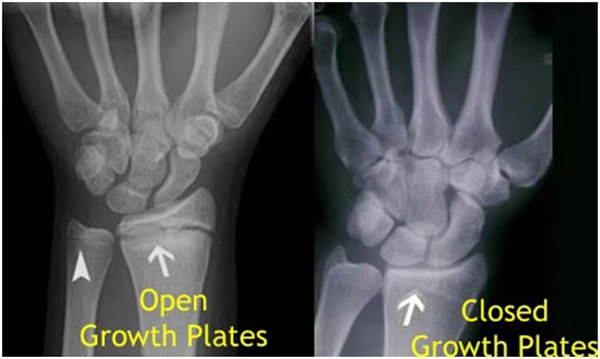

其實(shí)想要了解孩子的生長發(fā)育情況或者說孩子未來身高的趨勢,測骨齡是個好辦法。臨床上通常拍攝兒童的左手正位X光片 , 采用《中華-05》骨齡標(biāo)準(zhǔn)對手腕骨發(fā)育程度進(jìn)行骨齡評價。

我們都知道,人體的高矮是由骨骼的生長發(fā)育決定的,特別是下肢長骨。長骨呈長管狀,在長骨的兩端有一種專管骨骼生長的骺軟骨,它與干骺端之間有一盤狀軟骨結(jié)構(gòu)稱為骺板(線),在幼兒的X光片上表現(xiàn)為一條較寬的透光帶。 (見下圖)

未成年時隨著年齡的增加骺軟骨端不斷骨化,骨骼就不斷增長。當(dāng)骨骺線完全閉合時骨骼就停止生長,個子也就不再增長了。一般骨骺端完全閉合的年齡是18~20歲左右。